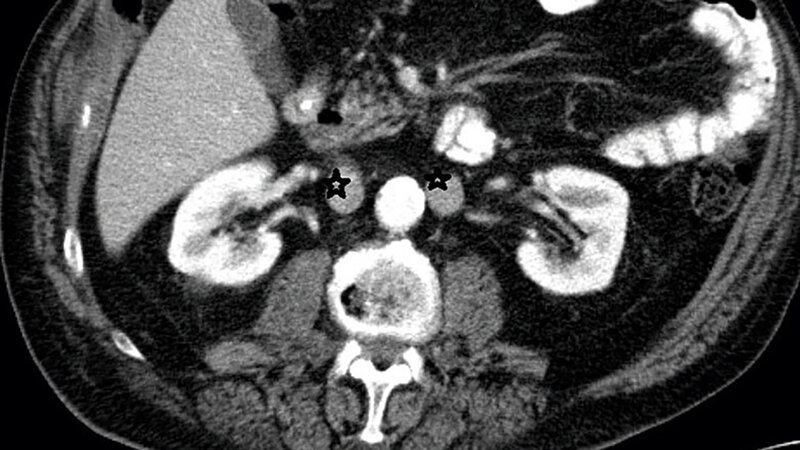

Die Doppelanlage der Vena cava inferior (VCI) ist die am häufigsten vorkommende Anomalie des venösen Gefäßes. Sie hat eine große Bedeutung bei retroperitonealen chirurgischen Eingriffen und venösen radiologischen Interventionen.

Duplication of the inferior vena cava (IVC) is the most common anomaly to affect the vena cava. Duplicated IVC has a significant relevance for retroperitoneal surgery and venous interventional radiology.